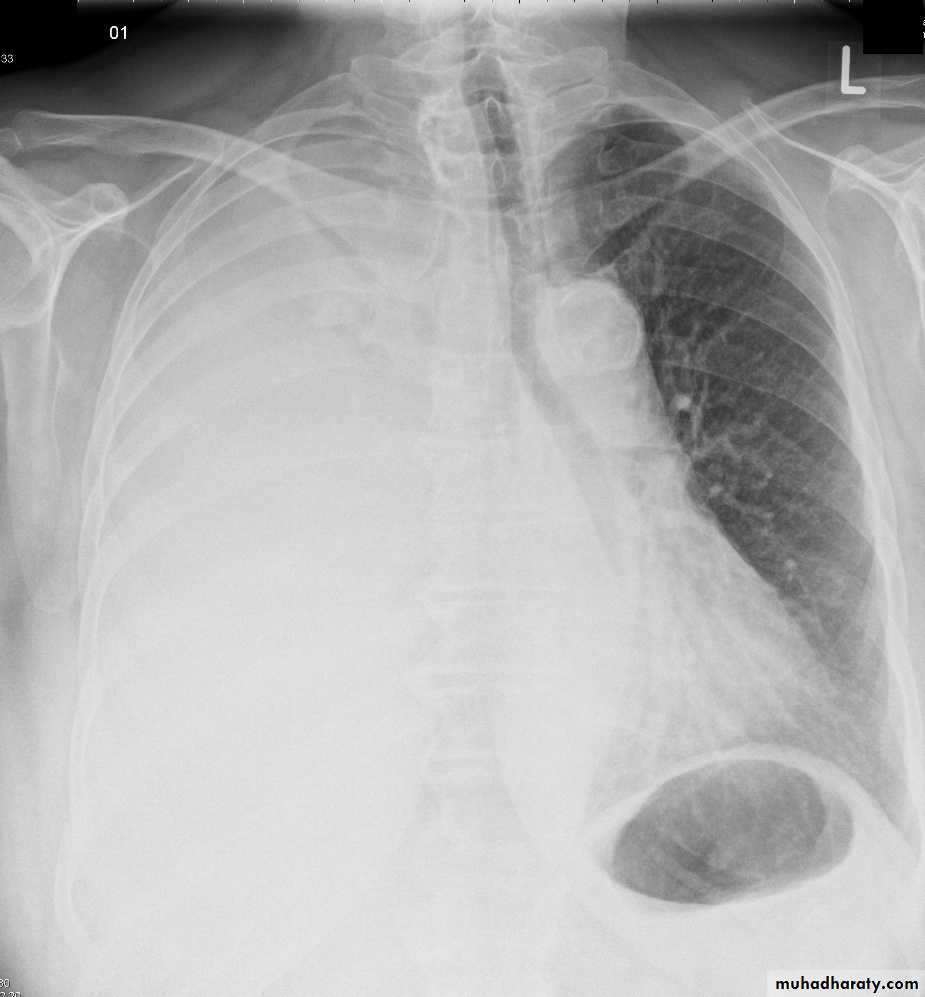

Total collapse total consolidation

Total collapse

48.opasified hemi thorax

49.total collapse